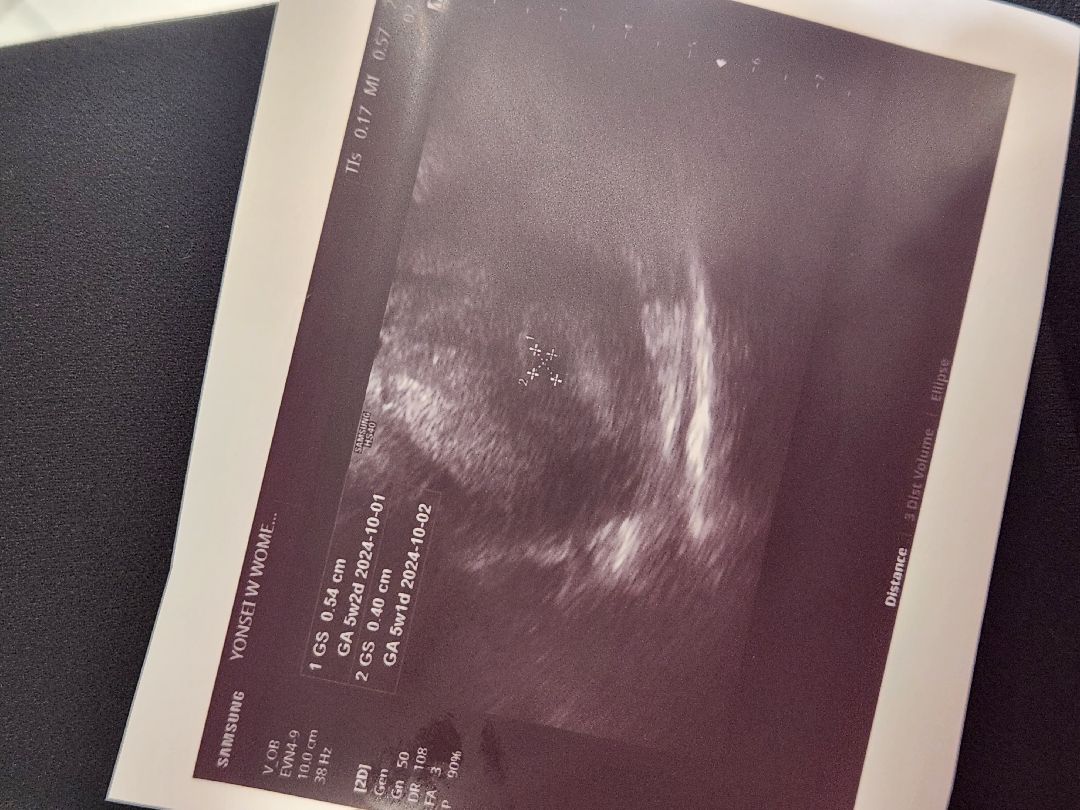

아가집 보댜🤗🩷

어제 4주4일차!! 3주차때 빠르게알게되고 먹덧,울렁거림 있었는데, 4주차에는 증상이없고 질염이 생가거같아 병원갔더니 초음파는아직 안해도될거같다 하셨는데 보시고나서 아가집이 5주3일차정도의 크기라고 하셨어요😍 저는 현재 배만 사방으로 콕콕 쑤시고있어용 오늘은 병원에서 임산부초기영양제 구매해쒀용✨️ 건강한 아가를위해소🧡🩷